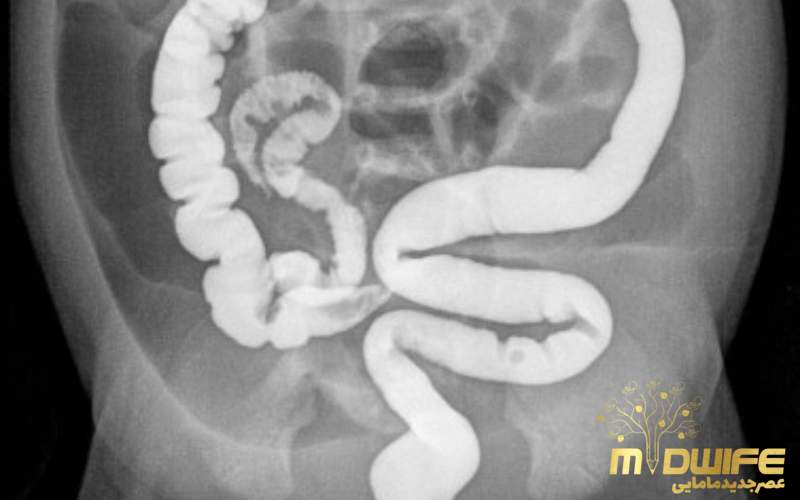

| تشخیص | معاینه فیزیکی، تصویربرداری (X-ray، سونوگرافی، تنقیه باریم)، آزمایش خون. |

- عکس ساده شکم (X-ray): بررسی وجود گاز و مایعات در قسمتهای مختلف روده، دیدن “Double Bubble Sign” (دو حباب گازی) در آترزیای دوازدهه

- سونوگرافی شکم: روش اصلی برای تشخیص انواژیناسیون روده، بررسی وضعیت پیچخوردگی یا ولوولوس

- تنقیه باریم یا گاستروگرافین (Barium/Contrast Enema): برای بررسی انسداد در روده بزرگ (مانند بیماری هیرشپرونگ)، ممکن است در بعضی موارد مانند انواژیناسیون، همزمان نقش درمانی هم داشته باشد